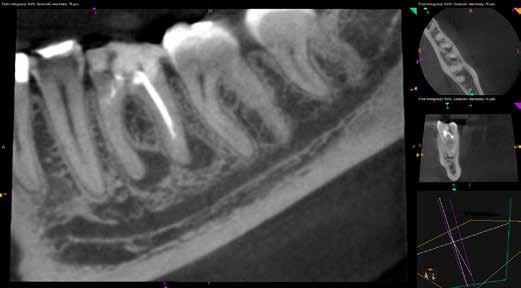

Mind a periapicalis röntgenfelvétel, mind a CBCT-felvétel igazolta, hogy a fragmentum mélyen a gyökércsatorna görbülete mögött, az apikális harmadban helyezkedik el a mesiobuccalis csatornában, valahol a mesiolingualis csatornával történő egyesülés után. Ezenfelül mind a mesialis, mind a distalis gyökércsúcs körül periapicalis gyulladás jelei voltak megfigyelhetőek (1–3. ábra). A betört eszköz nagyjából 5 mm-es hosszúsággal rendelkezett. A mesiolingualis csatornán keresztül a betört fragmentum mellett történő további gyökércsatorna-megmunkálást kockázatosnak ítéltük, mivel nagy esélyt láttunk rá, hogy így a másik eszköz is eltörik, amely pedig a gyökértömés elkészítését nehezítette volna. Azonban a SWEEPS technológiának és a biokerámia sealereknek köszönhetően más megoldási lehetőségek is nyitva álltak előttünk.

ábra: Kiindulási röntgen. A felvételen jól látható a betört eszköz és a periapikális lézió.

2. ábra: Kiindulási CBCT-felvétel. A betört eszköz mélyen a gyökércsatorna görbülete mögött található.

3. ábra: A betört eszköz vége jóval a mesiobuccalis és mesiolinguális csatorna egyesülésének pontja alatt helyezkedik el.